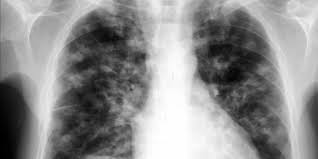

Seize (16) cas de tuberculose ont recensés dans la banlieue dakaroise, a révélé vendredi Adama Niang de l'Association de lutte contre cette maladie, lors du lancement d'une campagne de lutte, précisant que le quartiers Pikine, Guediawaye, Keur Massar, sont les plus touchés par cette pathologie.